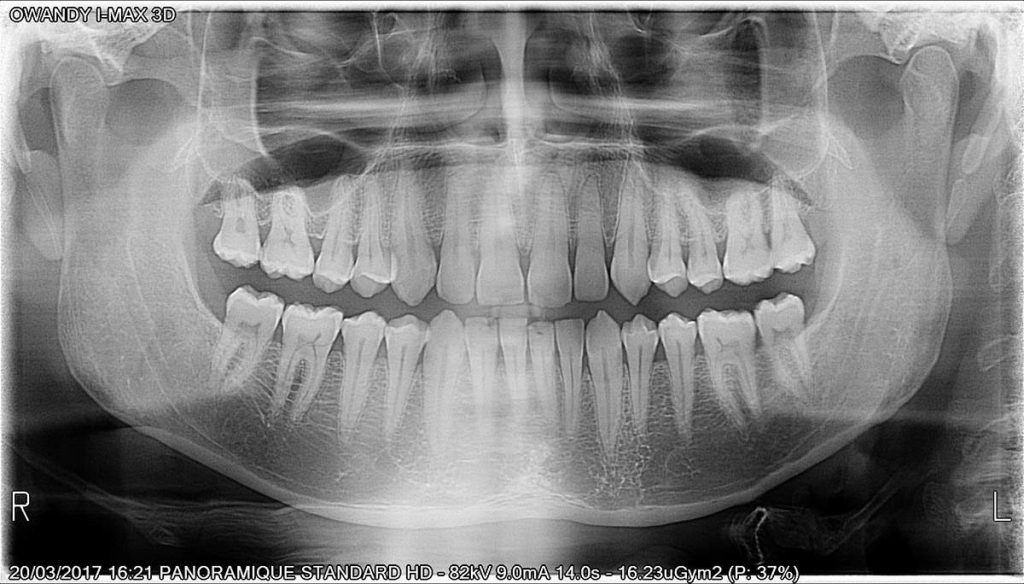

Calidad de imagen excepcional